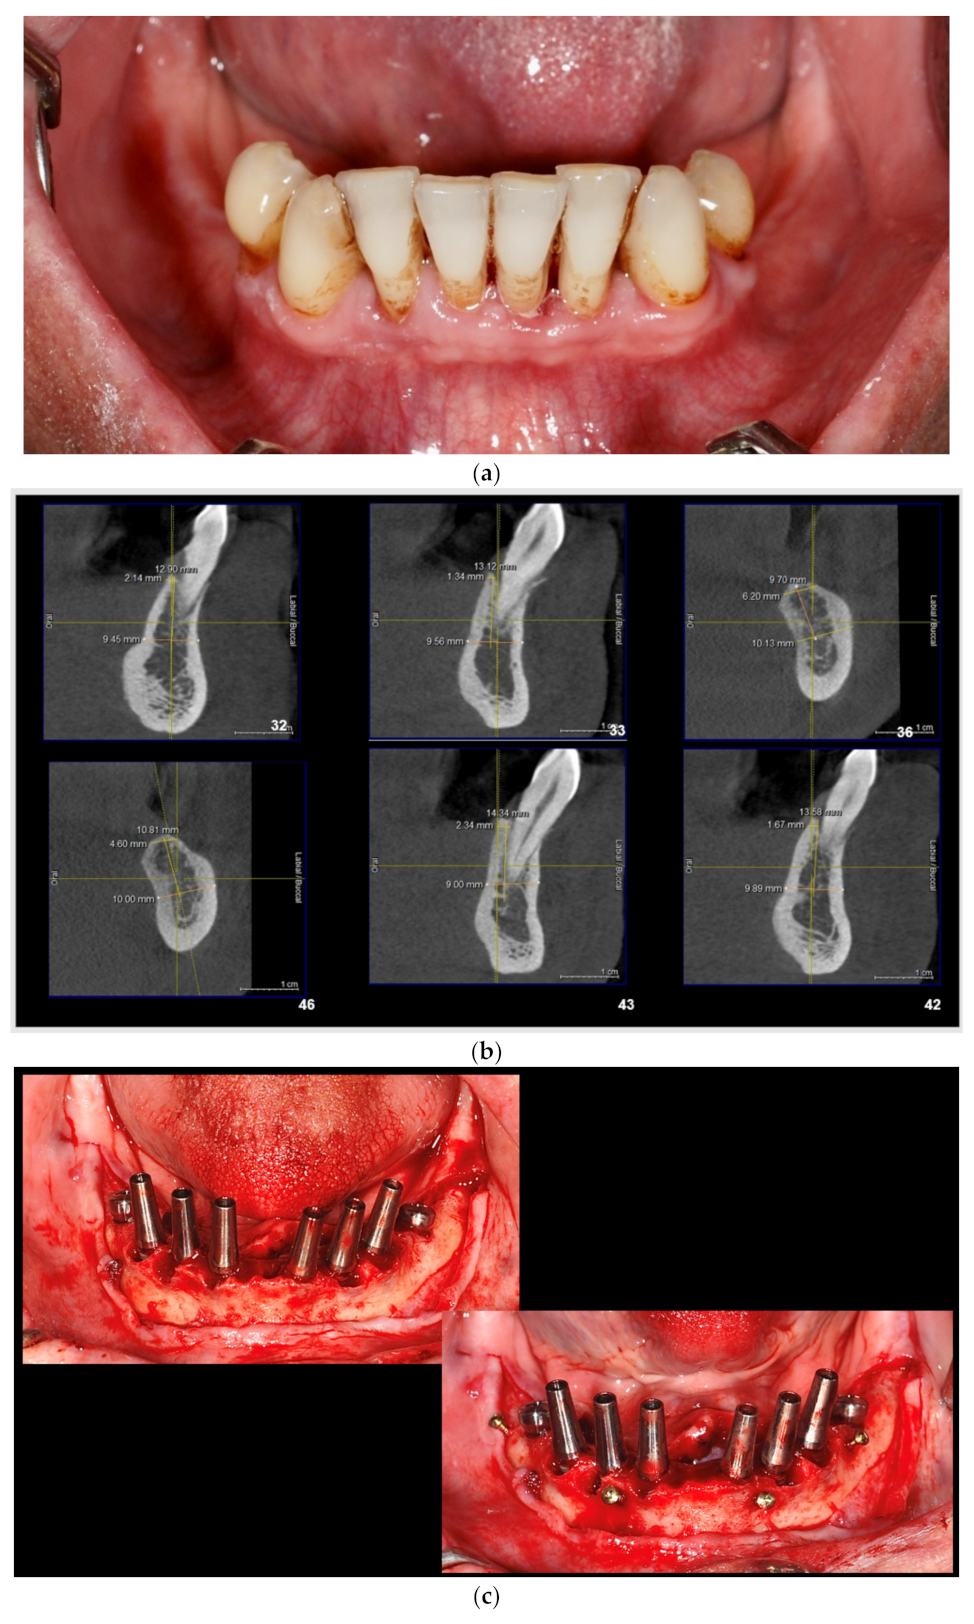

2.2. Description of Surgical Protocol

- (a)

- Dental implants placement simultaneously with alveolar augmentation by S-GBR technique (mixture of autogenous bone with autogenous bone 90:10; porcine pericardial collagen membrane) (test group);

- (b)

- Dental implants placement simultaneously with alveolar augmentation by S-GBR technique (mixture of bovine xenograft with autogenous bone 90:10; porcine pericardial collagen membrane) (control group).